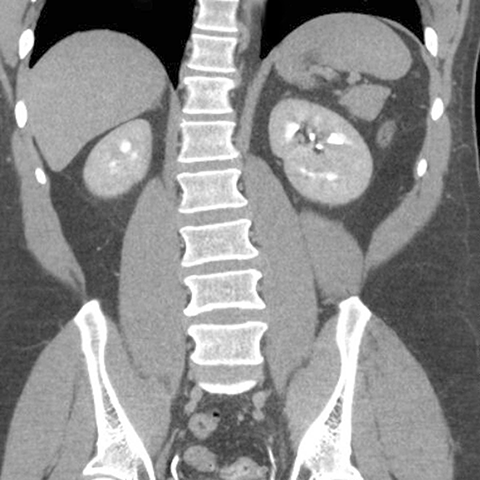

Normal spleen, coronal view (CT) [4 of 5]